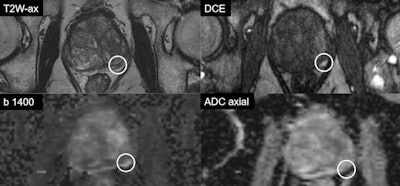

![T2-weighted image shows the prostate of a patient (age unknown) with an elevated prostate-specific antigen (PSA) level and previous negative transrectal ultrasound guided biopsies. Multiparametric MRI showed a large PI-RADS 5 lesion in the anterior part of the transition zone, which proved to be a clinically significant prostate cancer (International Society of Urologic Pathologists [ISUP] grade 3). Benign prostatic hypertrophy in the transition is visible as 'organized chaos' (blue area). All images courtesy of Prof. Jelle Barentsz, Dr. Maarten de Rooij, and Dr. Bas Israël.](https://img.auntminnieeurope.com/files/base/smg/all/image/2020/05/ame.2020_05_27_16_34_2157_2020_27_05_MRI_Insider_prostate_MRI_1.png?auto=format%2Ccompress&fit=max&q=70&w=400)